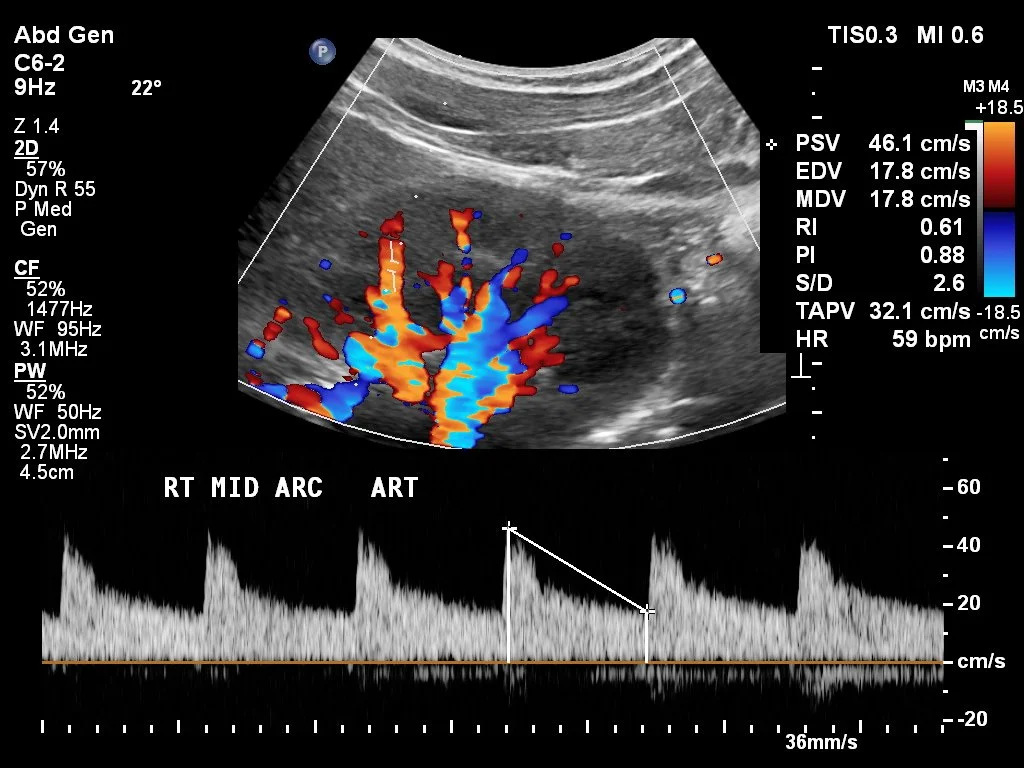

Renal Doppler

You need to check and make sure the “t” markers (as seen on first sequence in this photo) are at the top (red arrow) and bottom (green arrow) otherwise you will get wrong values.

The yellow line is the acceleration velocity and should be almost a straight line normally.

Renal Artery Stenosis US

• Normal Values

• PSV < 180 cm/s

• Proximal renal artery to aorta velocity ration < 3.5:1

• AT < 0.07

• RI < 0.08 and <5% difference between the two kidneys